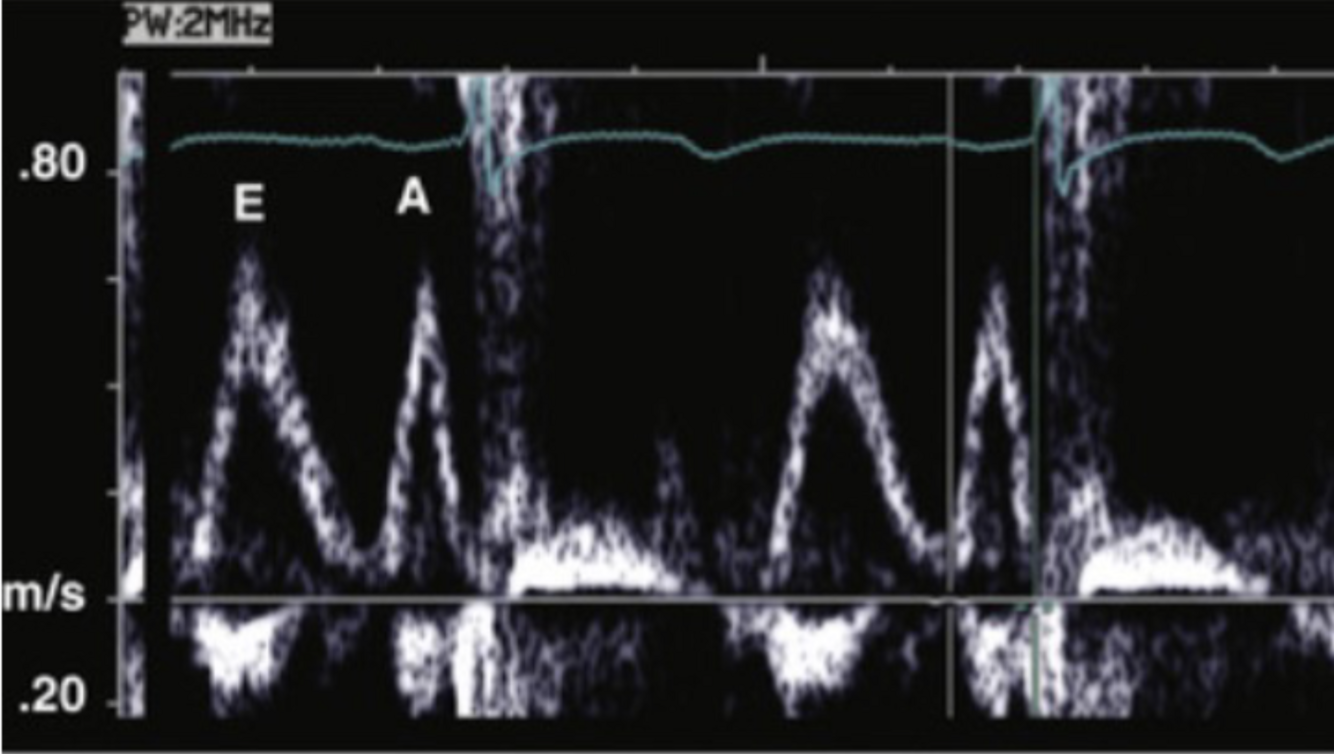

What normal flow pattern is this and in what view?

A

LV inflow (mitral), A4C